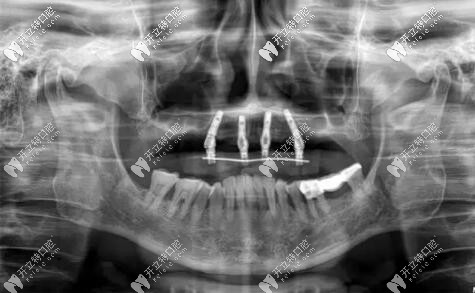

惠先生種植方案:前期A(yíng)LL-ON-4即刻負(fù)重,后期上頜竇外提升,同期植入兩顆種植體,做ALL-ON-6,馬龍一體橋。

目前已完成ALL-ON-4即刻負(fù)重,通過(guò)手術(shù)情況來(lái)看,效果確實(shí)比較好,作為一位地道老陜?nèi)?,惠先生的感激之情溢于言表?/p>